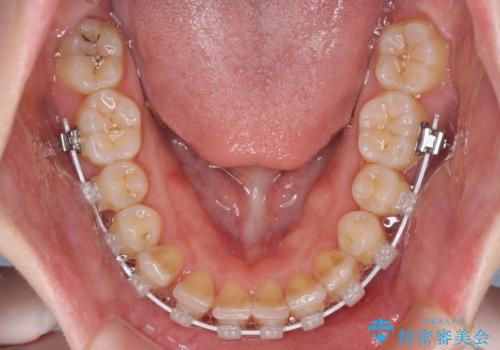

- 矯正装置

- 審美装置

半年もせずにインビザラインを全く使用することができなくなってしまったので、治療開始から1年ほどでワイヤー矯正へ変更することとなりました。

ワイヤー矯正へ変更してからはあっという間に治療が進み、1年弱で終えることができました。